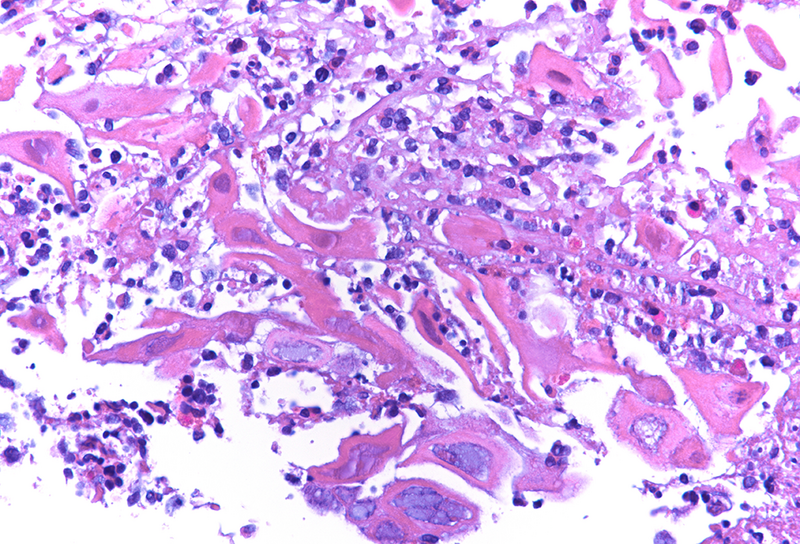

Cytology disclosed groups of squamous cells with enlarged ground-glass nuclei with homogenous chromatin pattern and multinucleation (Panels C-D). Upon histology, we observed multiple fragments of squamous epithelium with degenerating features admixed with inflammatory detritus. The nuclei of the squamous cells displayed ground-glass morphology as documented in the cytological material (Panels E-F). Immunostaining for Herpes simplex virus (HSV) I and II was positive (Panels G-H).

Histologically, the virus infects oesophageal squamous epithelium, typically at the superficial lateral margin of ulcers and erosions. The morphological diagnostic criteria include: (i) dense intranuclear eosinophilic to amphophilic round inclusion bodies with a clear halo separated from the nuclear membrane (Cowdry A inclusions), (ii) ground-glass nuclei with homogenous chromatin pattern, (iii) nuclear molding, (iv) multinucleated syncytia giant cells and (v) detached ballooning degeneration of infected cells. Immunohistochemistry studies is helpful in equivocal cases.